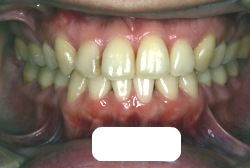

凸凹な歯並びのことを叢生といいます。矯正歯科に来院する患者様の主訴の中で、最も多いのが「配列の凸凹を真っ直ぐにしたい」というものです。歯の大きさと顎の大きさの調和がとれていないことが原因です。

凸凹を主体としたケースの場合、当院の平均治療期間は18ヶ月ですので、このケースは少し長めに経過しました。理由の一つは凸凹の程度がかなり重症だったと言うことですが、もう一つは、右下第2大臼歯が45度くらい前傾していたため、それを整直化させるために時間を要したと考えています。いずれにしても最終結果は大変よい状態と思います。

治療前は並びが乱れて見た目が悪いというのはもちろん問題ですが、歯科医学的に一番困るのは噛み合わせが悪いという点です。上下の犬歯(3番目の歯)は、上下的に離れた位置にあるため接触することができません。つまり歯としては存在していても、歯としては機能していないということです。